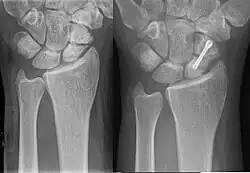

Dans le cas d'une fracture, trois techniques de soins sont applicables :

- immobilisation prolongée du poignet et de l'avant-bras (plâtre ou résine) pendant 90 jours,

- fixation en chirurgie ambulatoire par technique percutanée,

- vissage en chirurgie classique à ciel ouvert.

Les techniques applicables dépendent du type de fracture et de sa localisation sur l'os. Pour les fractures non déplacées, principalement celles du corps du scaphoïde, la technique percutanée tend à se développer. Elle s'opère sous anesthésie locale, sans hospitalisation du patient, et dure environ 20 à 30 minutes. Ses résultats sont excellents, et la durée d'immobilisation consécutive est réduite à environ deux semaines (contre 8 à 12 semaines sans intervention). Toutefois, un traitement par immobilisation, dans les formes médiales, avec contrôle radiologique et intervention chirurgicale s'il n' y a pas de signe de consolidation, expose à moins de complications qu'une chirurgie immédiate, avec un résultat fonctionnel aussi bon[10].